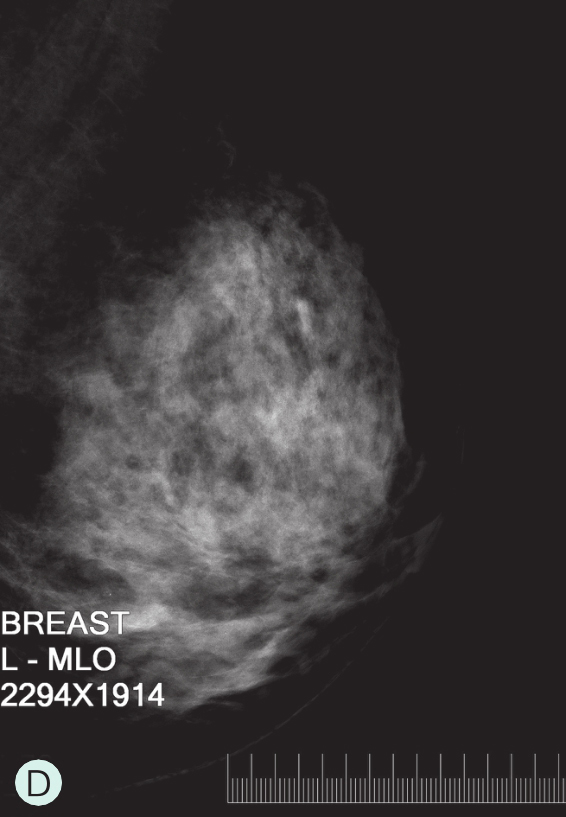

D级:极度致密型(降低乳腺钼靶摄影的敏感性)(图1-3-1D、图1-3-2D、图1-3-3D)。

图1-3-3 乳腺MRI不同乳腺密度

A.脂肪型;B.散在致密型;C.不均匀致密型;D.极度致密型